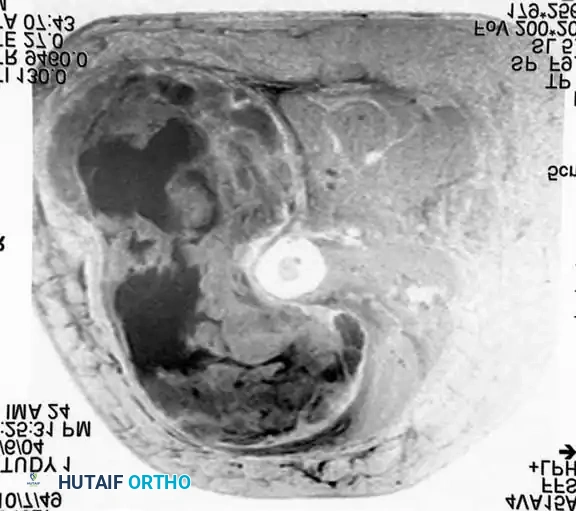

Imaging:

Conventional radiographs may demonstrate a non-specific soft-tissue density but are usually normal. MRI reveals a well-circumscribed mass that is typically isointense to muscle on T1-weighted images and hyperintense on T2-weighted images. Central necrosis is a hallmark of larger, high-grade tumors.

Axial MRI showing a large soft-tissue mass in the thigh with mixed signal intensity, characteristic of UPS/MFH.

Coronal MRI demonstrating the proximal-distal extent of the tumor within the muscular compartment.